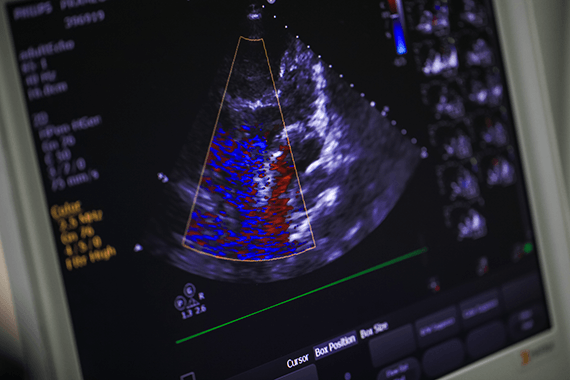

Tests are used to diagnose a heart condition or to see how healthy your heart is. Find out what to expect from some of the most common tests.